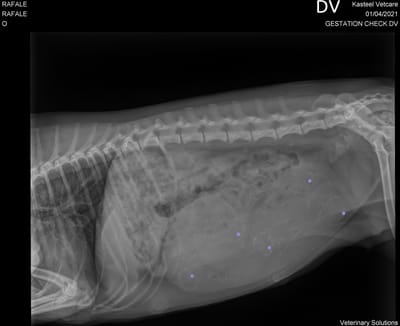

Confirmation de gestation

Les chiots sont prévus pour mi-avril